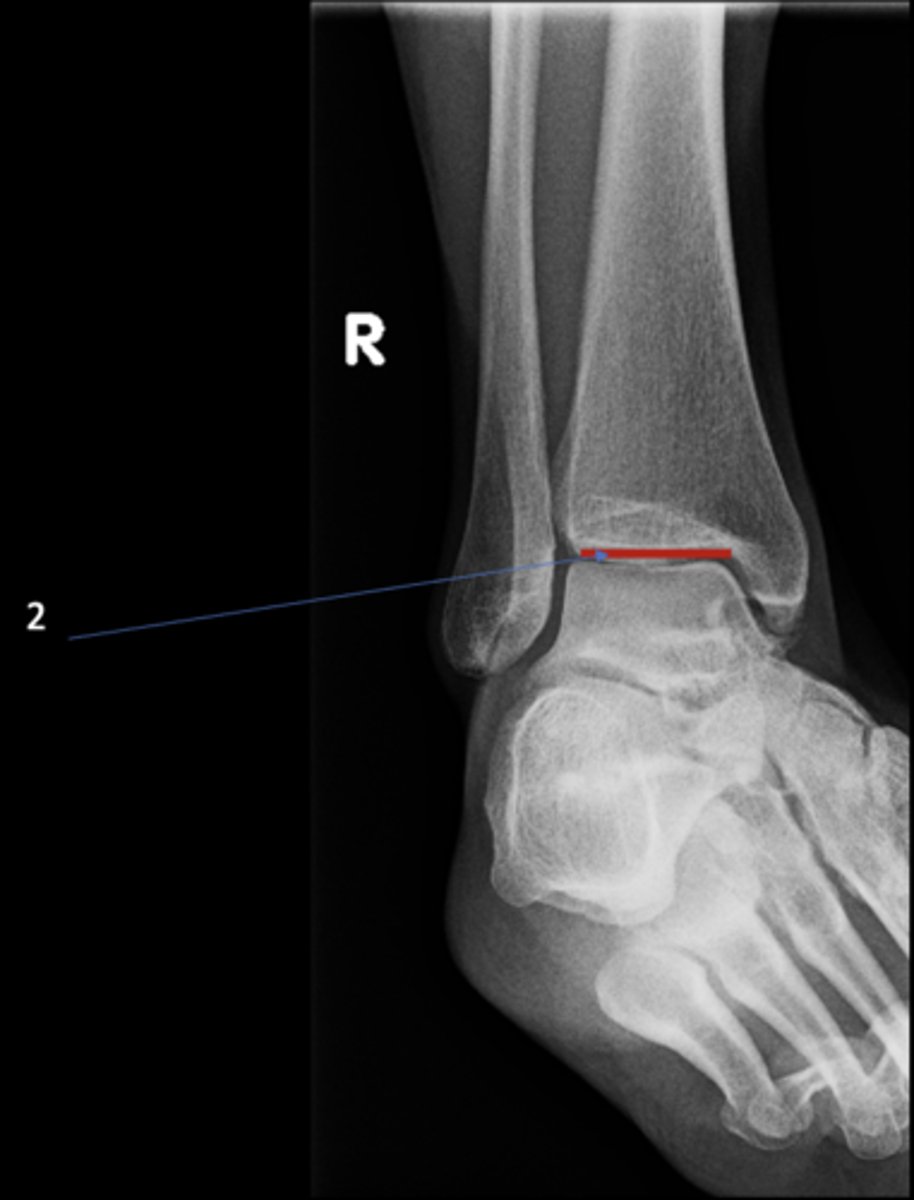

Right AP ankle

View?

Lateral malleolus

ID 11

Tibial plafond

ID 12

Trochlea of talus

ID 13

Distal tibiofibular joint

ID 14 (joint)

Tibiotalar joint

ID 17 (joint)

Right medial oblique ankle

ID 1

ID 2

ID 3

Talocalcaneal joint

ID 4 (joint)

Sinus tarsi

ID 8

Base of 5th metatarsal

ID 9

Medial malleolus

ID 10